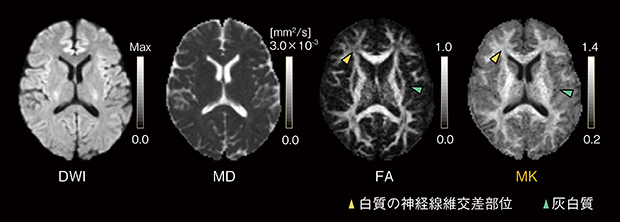

尖度テンソルから導かれる指標として,空間方向の平均値であるMean Kurtosis(MK),拡散テンソルの主軸方向のAxial Kurtosis(K∥),主軸に垂直な方向のRadial Kurtosis(K⊥)が使用されます。従来,白質の描出に用いられているFAでは,神経線維交差部位での輝度低下など,正常でも生じるコントラスト変化が課題でした。また,灰白質では異方性がないため,コントラストが得にくいという課題がありました。これに対し,MKは平均的な制限拡散を表しているため,前述のような神経線維交差部位での白質のコントラスト変化が少なく,また,灰白質でのコントラストが高いため,病変のわずかな変化を可視化できると考えられています(図3)。

図3 Diffusion Tensor Imaging(DTI)の指標Fractional Anisotropy(FA)とDiffusion Kurtosis Imaging(DKI)の指標Mean Kurtosis(MK)の比較

FAマップでは白質の神経線維交差部位での輝度低下と灰白質のコントラスト消失が見られます。これに対し,MKマップでは白質の均質性向上と灰白質のコントラスト上昇が確認できます。